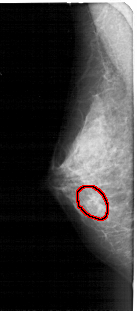

A_1475_1.LEFT_MLO

FILE: A_1475_1.LEFT_MLO.OVERLAY

TOTAL_ABNORMALITIES 1

ABNORMALITY 1

LESION_TYPE CALCIFICATION TYPE AMORPHOUS DISTRIBUTION CLUSTERED

ASSESSMENT 4

SUBTLETY 3

PATHOLOGY BENIGN

TOTAL_OUTLINES 1

BOUNDARY